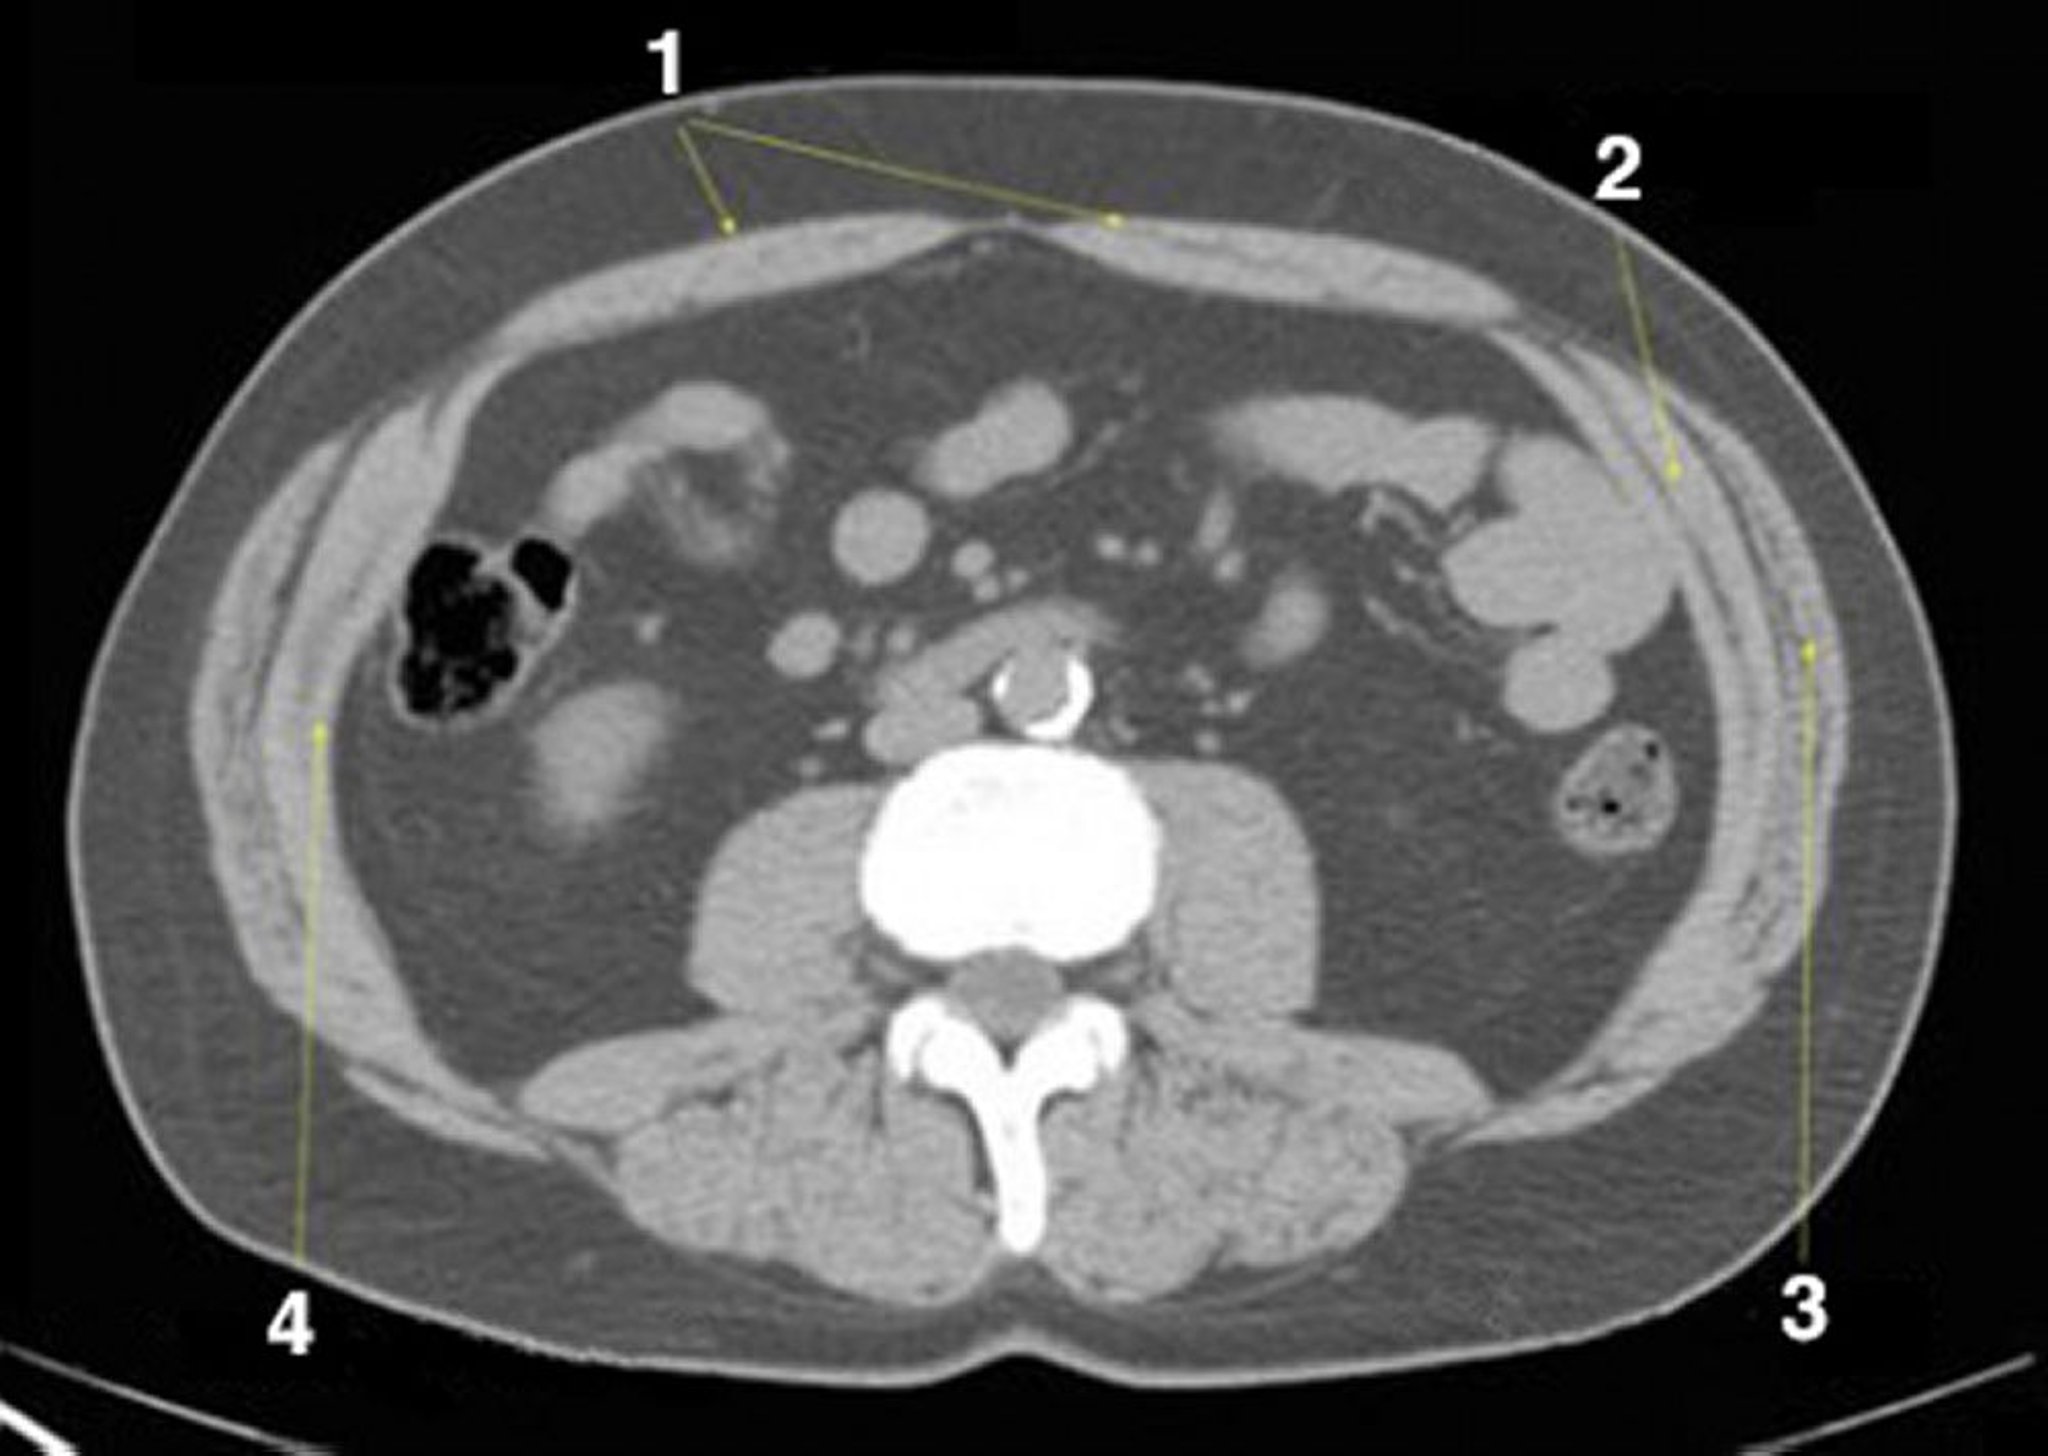

TC senza contrasto dell'addome e della pelvi che mostra un'anatomia normale (Slide 19)

1 = retto addominale; 2 = interno obliquo; 3 = esterno obliquo; 4 = addominale trasversale.